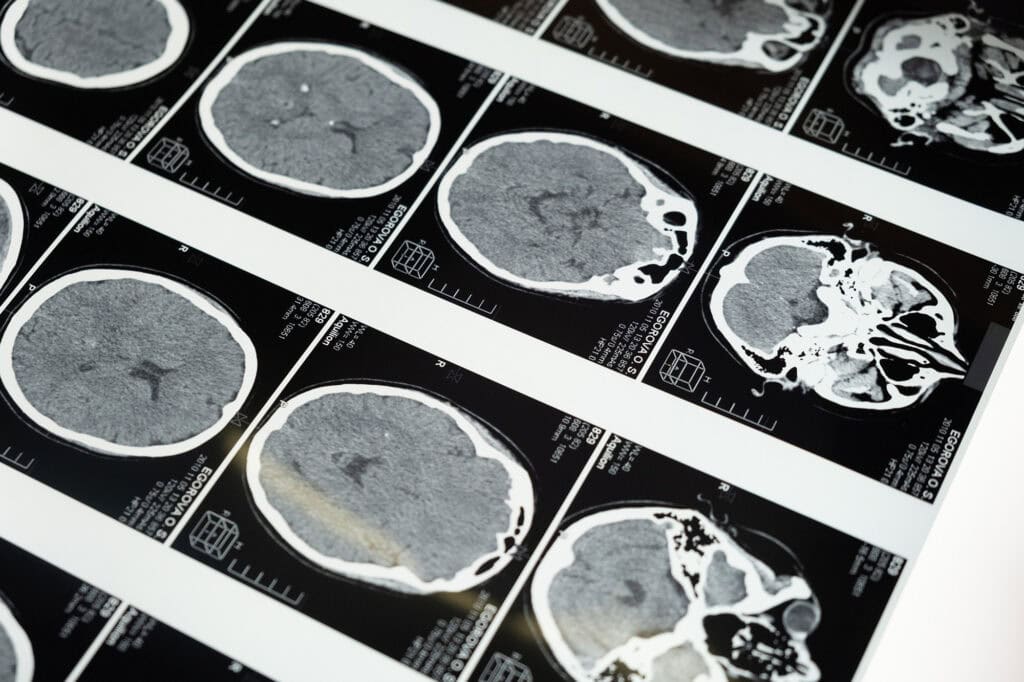

Beyin Kanaması Teşhisi Nasıl Olur?

Beyin kanamasının teşhisi tipik olarak tıbbi öykü değerlendirmesi, fizik muayene ve görüntüleme çalışmalarının bir kombinasyonunu içerir. Bilgisayarlı tomografi (BT) taramaları ve manyetik rezonans görüntüleme (MRI), beyni görselleştirmek ve kanama belirtilerini tespit etmek için yaygın olarak kullanılır.

Kan damarlarındaki anormallikleri belirlemek için anjiyografi yapılabilir. Bu teşhis prosedürleri, sağlık profesyonellerinin kanamanın yerini, boyutunu ve nedenini belirlemesine yardımcı olarak uygun bir tedavi planı geliştirmelerine yol gösterir.